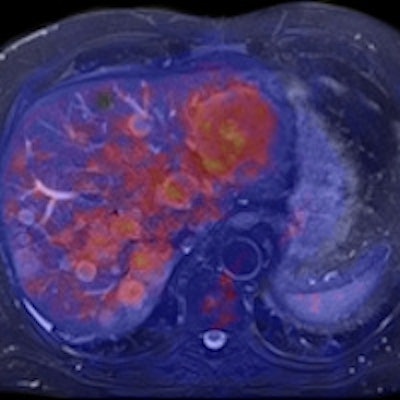

Left: PET tracer uptake in the liver can be combined with the time-varying enhancement of dynamic MR scans to visualize hepatic tumor characteristics. Right: MR and PET come together to support tumor staging. In this case, high-resolution MR provides a clear image of the pathology within the pelvic structure, while PET displays the hypermetabolism component of the lesion. Images courtesy of Siemens.Drzezga believes that combining the two modalities offers a number of clinical advantages, not least in eliminating the need for separate diagnostic examinations. Furthermore, the exact anatomical registration of structural and functional/molecular information may improve allocation of suspect findings and improve image quality, for example by motion correction of regions of the body that do not remain rigid during examination. The Munich team will also be exploring how the performance of PET/MR compares with that of PET/CT. There is some evidence that the superior soft-tissue contrast achievable with the newer system will offer significant benefits, even before physicians consider the safety issues involved with any radiation-based imaging technology such as PET/CT, Drzezga suggested.